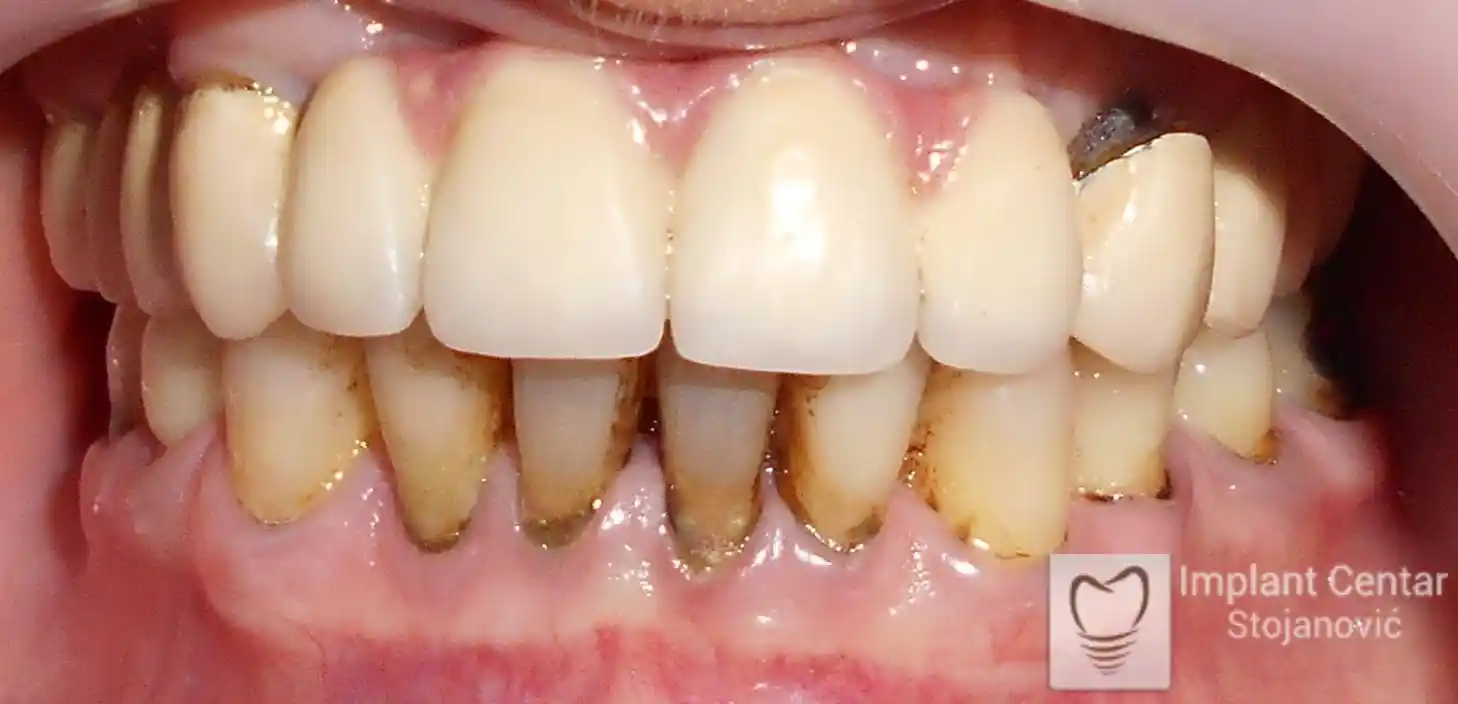

Na slikama 1, 2, 3 , 4  i  5 prikazan je izgled pacijenta pre početka terapije. Nakon detaljne kliničke i radiološke analize, doneta je odluka o vađenju zuba loše biološke vrednosti, dok su bezuba polja sanirana ugradnjom dentalnih implantata.

Nakon ugradnje implantata i pripreme preostalih zuba, pacijentu su izrađene fiksne privremene krunice, čime je postignut eugnatan zagriz već nakon jednog dana (slika 8, 9 i 10). Tokom perioda osteointegracije, pacijent se postepeno privikavao na novi položaj vilica i zagriz.

Po završetku perioda integracije, izrađeni su definitivni cirkonijum-keramički mostovi, čime je postignuta potpuna rekonstrukcija zagriza, kao i značajno poboljšanje estetike i oralne funkcije (slika 12, 13, 14 i 15).